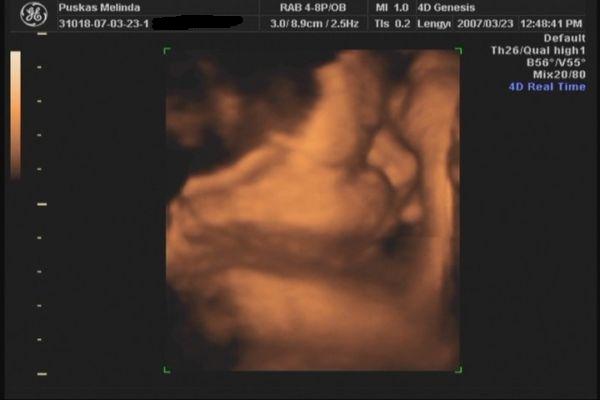

Tegnap voltunk 4D-n. gyönyörű egészséges 31 dekás kislány. :D A Lara Boglárka nevet kapja tőlünk. :) egy kép róla meg egy a pocakról. :)

Kép Kép